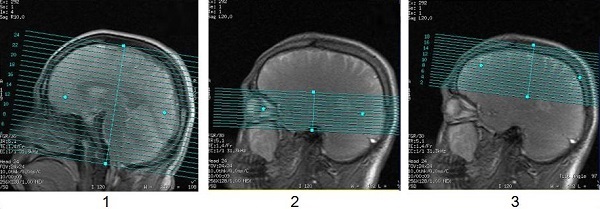

For a head scan with a feet first position, the alignment light is positioned at the extreme superior edge of the landmark position, which is approximately 23 cm from the edge of the cradle.

If the graphic Rx slices are positioned at the superior end of the FOV, then a message may be posted indicating that the scan cradle could not go far enough into the bore to complete the scan.

| Number | Description |

|---|---|

| 1 | Entire brain graphic prescription does not present a problem. |

| 2 | Orbit graphic prescription does not present a problem. |

| 3 | Scan prescription centered at the top of the head presents a problem and an error message is posted indicating that the scan table cannot go into the bore far enough to complete the requested prescription. Feet first positioning in this scenario cannot be completed. |